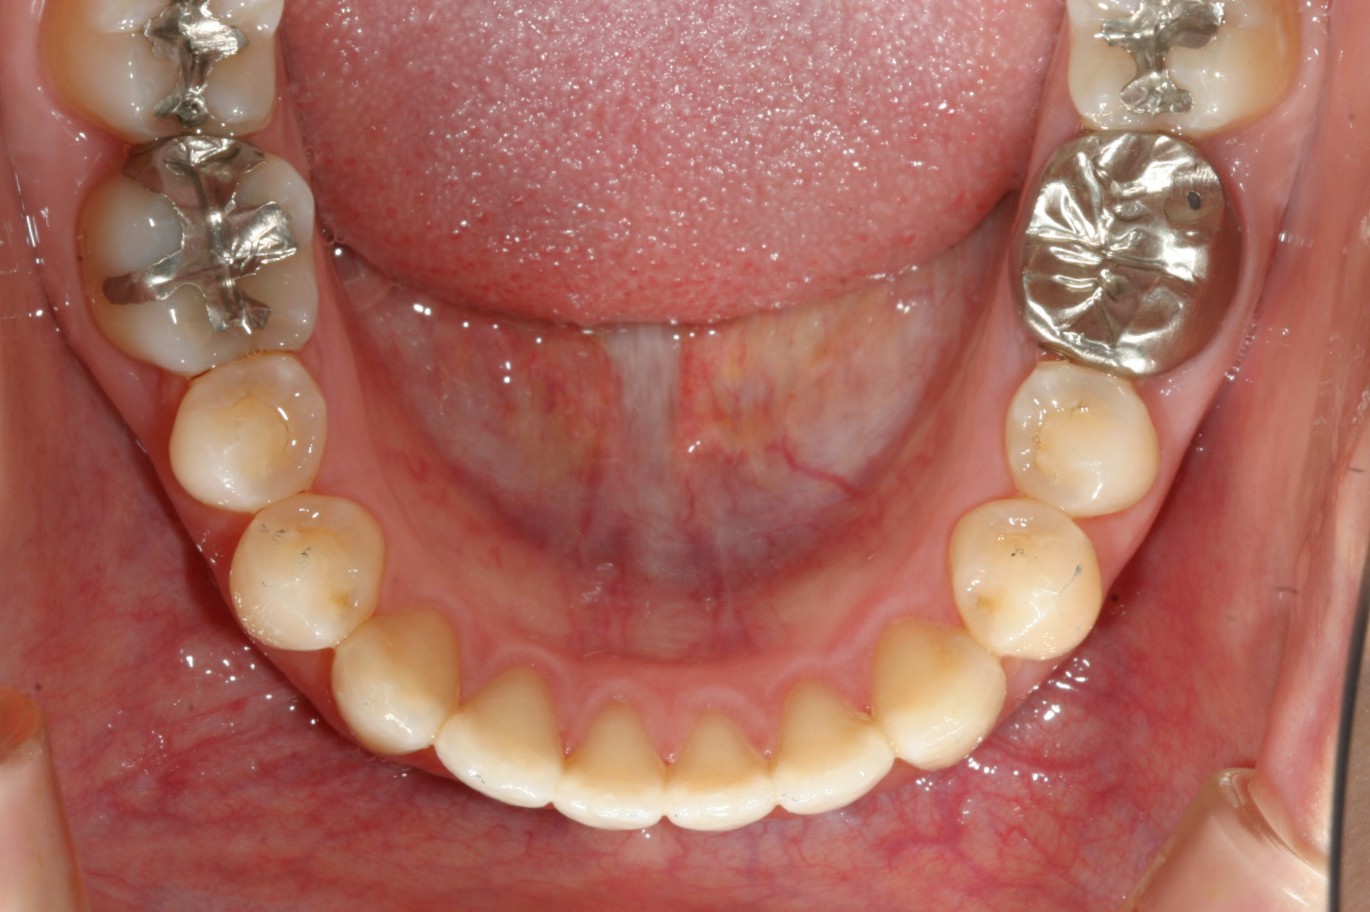

今回のケースは全体的に歯と歯の間がすきっ歯になっている為、前方に飛び出した感じになっています。

この隙間を閉じる事によりこの様に出っ歯感を改善しました。

インビザラインでは今回のケースの様に隙間を閉じるケースが一番得意です。

ただ閉じるだけでなく多少IPRする事により隙間をさらに少し調整し出っ歯感を改善しています。

ここまで歯を入れればもう出っ歯とは言われないですね!